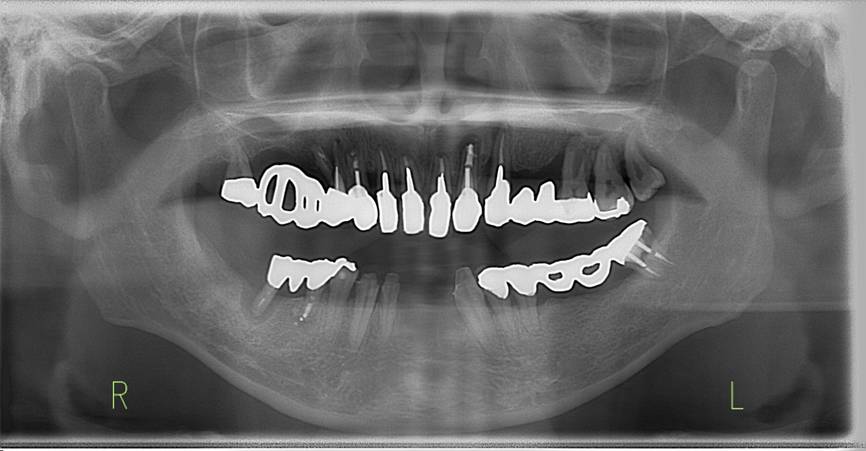

術前パノラマレントゲン写真。根の周りが黒くなり、骨がなくなっていることがわかります

治療後。歯周病で失われた骨が回復しています。使用インプラントはスプラインツイストです。

インプラント装着後6年。順調に経過しています。12か月毎のメインテナンスをしています。